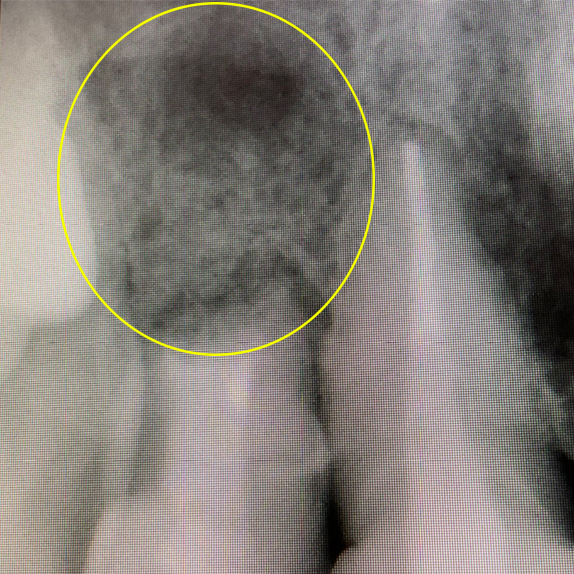

CASE 07 マイクロエンド(精密根管治療)+歯根周囲掻爬(歯周外科)

歯ぐきがよく腫れる主訴で来院。レントゲン写真の術前を見ると大きな影が確認できます。この部分に嚢胞(のうほう)がある状態です。マイクロエンドと歯根周囲掻爬(歯周外科)をすることで改善したケースです。